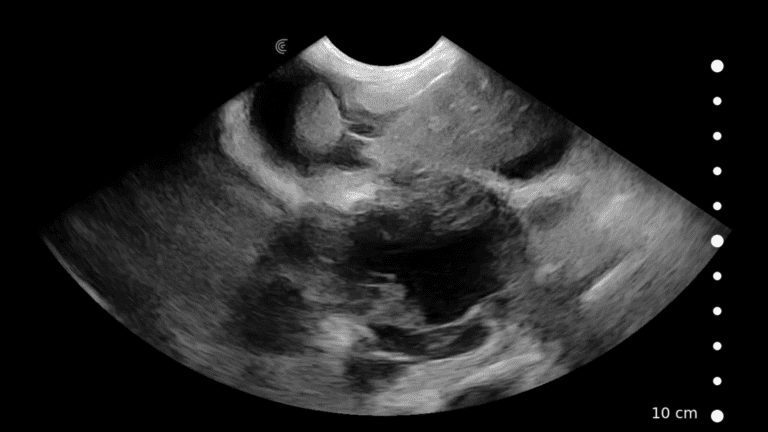

Canine: Adrenal Glands

In this video Dr. Camilla Edwards shares her technique for imaging the adrenal glands in a dog. She provides useful landmarks to identify their location, and describe the ultrasound appearance of normal adrenals.